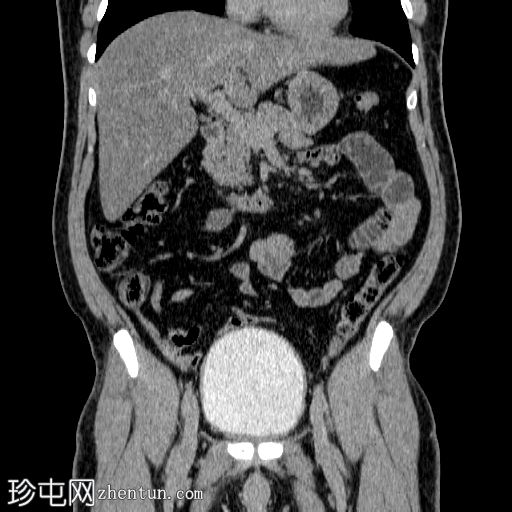

冠状位增强扫描

动脉期

在左侧输尿管膀胱连接处可见一枚24×15 mm的大膀胱结石。膀胱壁轻度弥漫性增厚,厚度约6 mm,提示膀胱炎。

左肾上极发现一单纯性皮质囊肿,Bosniak I 型,大小为 13 mm。

可见多个副脾(脾小体),位于主脾实质的上方和下方,在影像学各期均表现出与脾脏相似的衰减值。

肝脏弥漫性脂肪浸润。